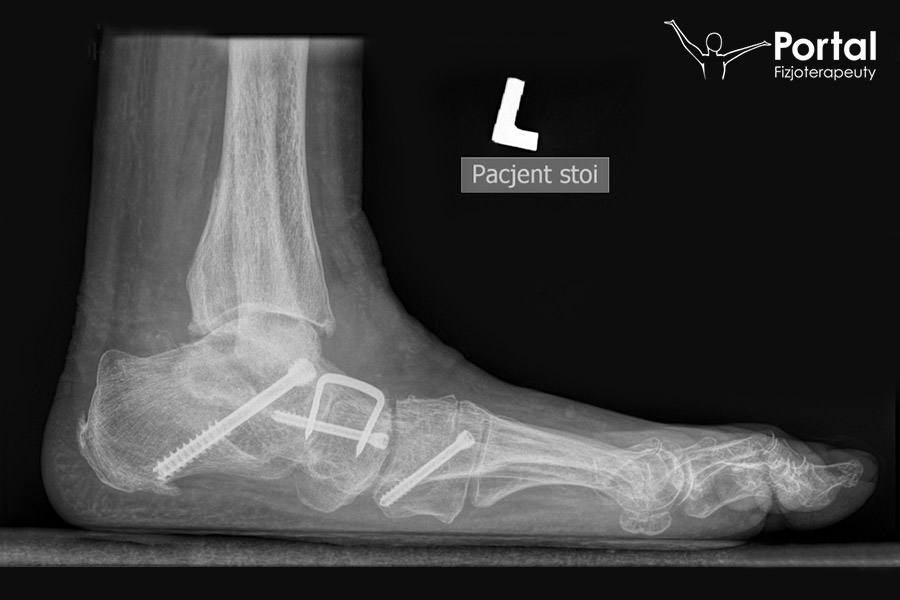

W większości przypadków płaskostopia wystarczy skorygować ustawienie I kości śródstopia poprzez jej przemieszczenie w kierunku pozostałych kości oraz obniżenie. Dodatkowo unosi się lub skraca kości śródstopia II-IV. W fizjologicznych warunkach kości śródstopia ustawiają się nieco skośnie do podłoża, w związku z czym już samo zmniejszenie ich długości automatycznie powoduje uniesienie głów kości śródstopia. Do procedur operacyjnych mających na celu korekcję płaskostopia podłużnego można zaliczyć:

- artroerezę podskokową z implantem;

- osteotomię ślizgową pięty;

- osteotomię Cottona;

- osteotomię Evansa;

- augmentację lub rekonstrukcję niewydolnego ścięgna mięśnia piszczelowego tylnego;

- artrodezę stawu skokowego.

Natomiast do procedur operacyjnych, których celem jest korekcja płaskostopia poprzecznego, zalicza się:

- osteotomię DMMO;

- osteotomię Weila;

- korekcję towarzyszących deformacji palców stopy (w tym m.in. palucha koślawego czy palców młotkowatych).

Celem operacji jest trwała strukturalna korekcja płaskostopia oraz poprawa przetaczania stopy w trakcie chodu. Przy prawidłowo wykonanej operacji stawy w obrębie stopy i całej kończyny dolnej zaczynają pracować w bardziej fizjologicznym ułożeniu, zmniejszając przeciążenie chrząstki stawowej i przeciwdziałając wczesnym zwyrodnieniom. Operacja płaskostopia odbywa się w znieczuleniu miejscowym (wyłącza się czucie w kończynie dolnej).